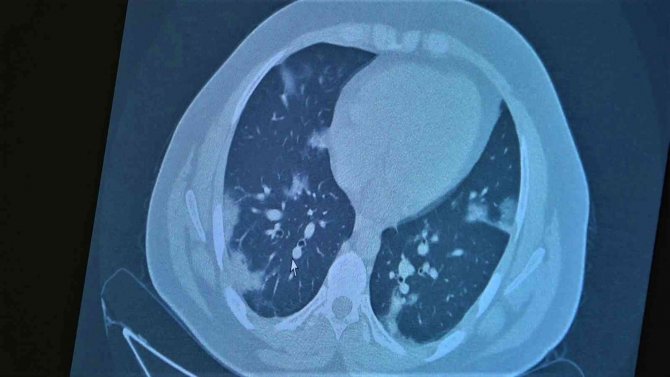

Çocukların akciğer tomografilerini inceleyen Özkaya, "11 yaşında kovid pozitif bir öğrencimiz, yüksek ateş ve nefes darlığı ile bize geldi. Ciddi akciğer tutulumu var. Geçen yıl "bu çocuklar hastalıktan etkilenmiyor" diyorduk. Bu çocukta görüyorsunuz buzlu camlar ve konsolidasyon alanlarla seyrediyor. Geçen yıl bu şekilde çok çocuk görmüyorduk. Önümüzdeki aylarda bu şekilde devam ederse çocuklarımızı kaybetmeye bile başlayabiliriz. 14 yaşında pozitif olan bir diğer çocuğumuz ise aşı randevusu almış ama aşısını olmadan ateş ve öksürükle başvurdu. Halen şanslıyız. Çocuklar çok hızlı tedaviye yanıt veriyor. Düzeldi. Çekilen tomografisinde ise bilaterel yaygın tutulumları vardı. Bu ise 24 yaşında genç hastanın akciğer tomografisi. Bu kişide yaygın akciğer tutulumları görüldü. Bunu da tedavi ettik. Önümüzdeki aylarda ne getirecek ne götürecek beraber göreceğiz. Özellikle havaların soğumasıyla kapalı ortamlarda geçilen zamanın ve kalabalıkların etkisiyle vaka sayılarının önümüzdeki günlerde artacağını biliyoruz. Şu an gerçekten hastalık gençlerde 30 -40 yaş altı gençlerde görülmeye başladı. Poliklinik şartlarında olanların büyük bir kısmı 30 yaş altı hastalar. Servislerde yatanlarda orta yaş ve altı nüfus. Yoğun bakımda yatanların büyük bir kısmı ise aşısız erişkin insanlardan oluşuyor" diye konuştu.